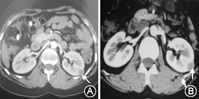

2. 患者2016年查肾上腺强化CT及肾动脉CTA提示双侧肾上腺未见确切异常,左肾下极结节影,直径14.7 mm,囊肿可能性大,请结合临床及超声(图1A)。2017年复查肾上腺强化CT,提示双侧肾上腺CT增强未见明显异常,左肾下极实性结节,直径15 mm,考虑肿瘤性病变,结合病史,肾素瘤可能性大(图1B)。

卧、立位DRC均明显升高,ALD正常,血钾低,腹部增强CT显示肾上腺正常;左肾下极一实性结节,直径1.5 cm,密度呈斑点状;增强后轻微延迟成像,考虑肾素瘤可能性大。